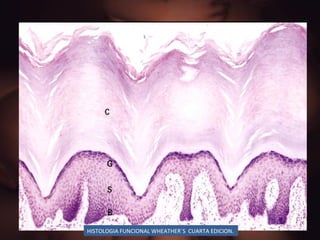

CITODIFERENCIACION EPIDERMICA Estrato basal:  Células en mitosis, expresión de moléculas de adhesión a matriz Estrato espinoso:  Células sintetizan citoqueratinas Integrinas de la matriz Desmosomas integrinas MAC Estrato granuloso: Sintetiza queratohialina (histidina y sulturos) Filagrina Estrato corneo:  Pierden el núcleo, sacos  de    citoqueratinas unidas /  filagrinas

HISTOLOGIA FUNCIONAL WHEATHER`S  CUARTA EDICION.